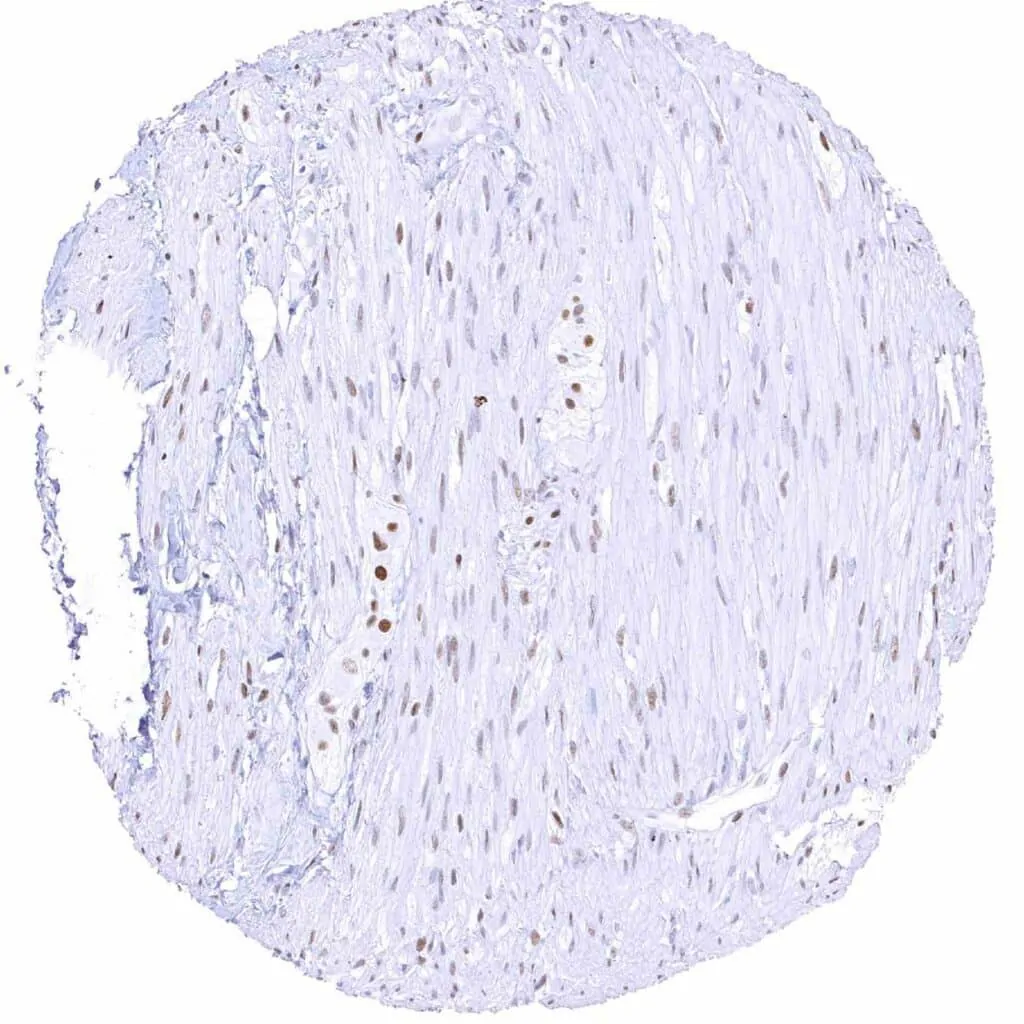

Aorta, media – Moderate TLE1 positivity of a subset of spindle cells in the media

Uterus, myometrium – Weak to moderate TLE1 positivity of smooth muscle cells